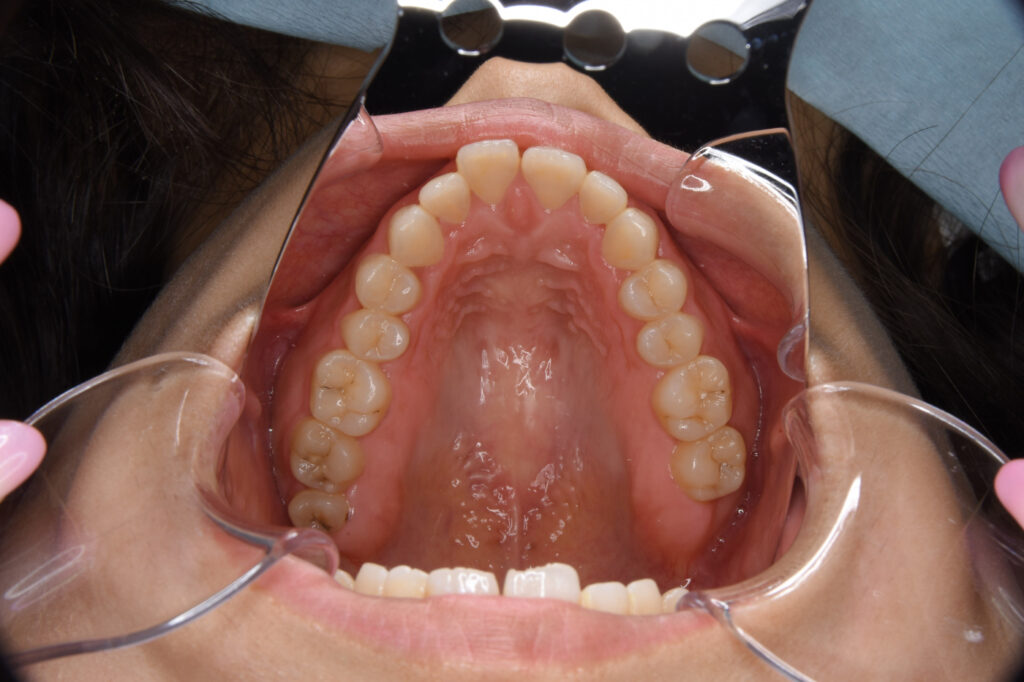

前歯が出ているために口が閉じにくく、口元が目立つことに悩まれていた方です。早期の改善を望まれていたため、抜歯とワイヤー矯正、歯科矯正用アンカースクリューによる治療を実施しました。

治療の内容上顎左右側第一小臼歯を抜歯。上顎舌側下顎唇側ワイヤー矯正装置、口蓋に歯科矯正用アンカースクリュー2本を用いた矯正治療。